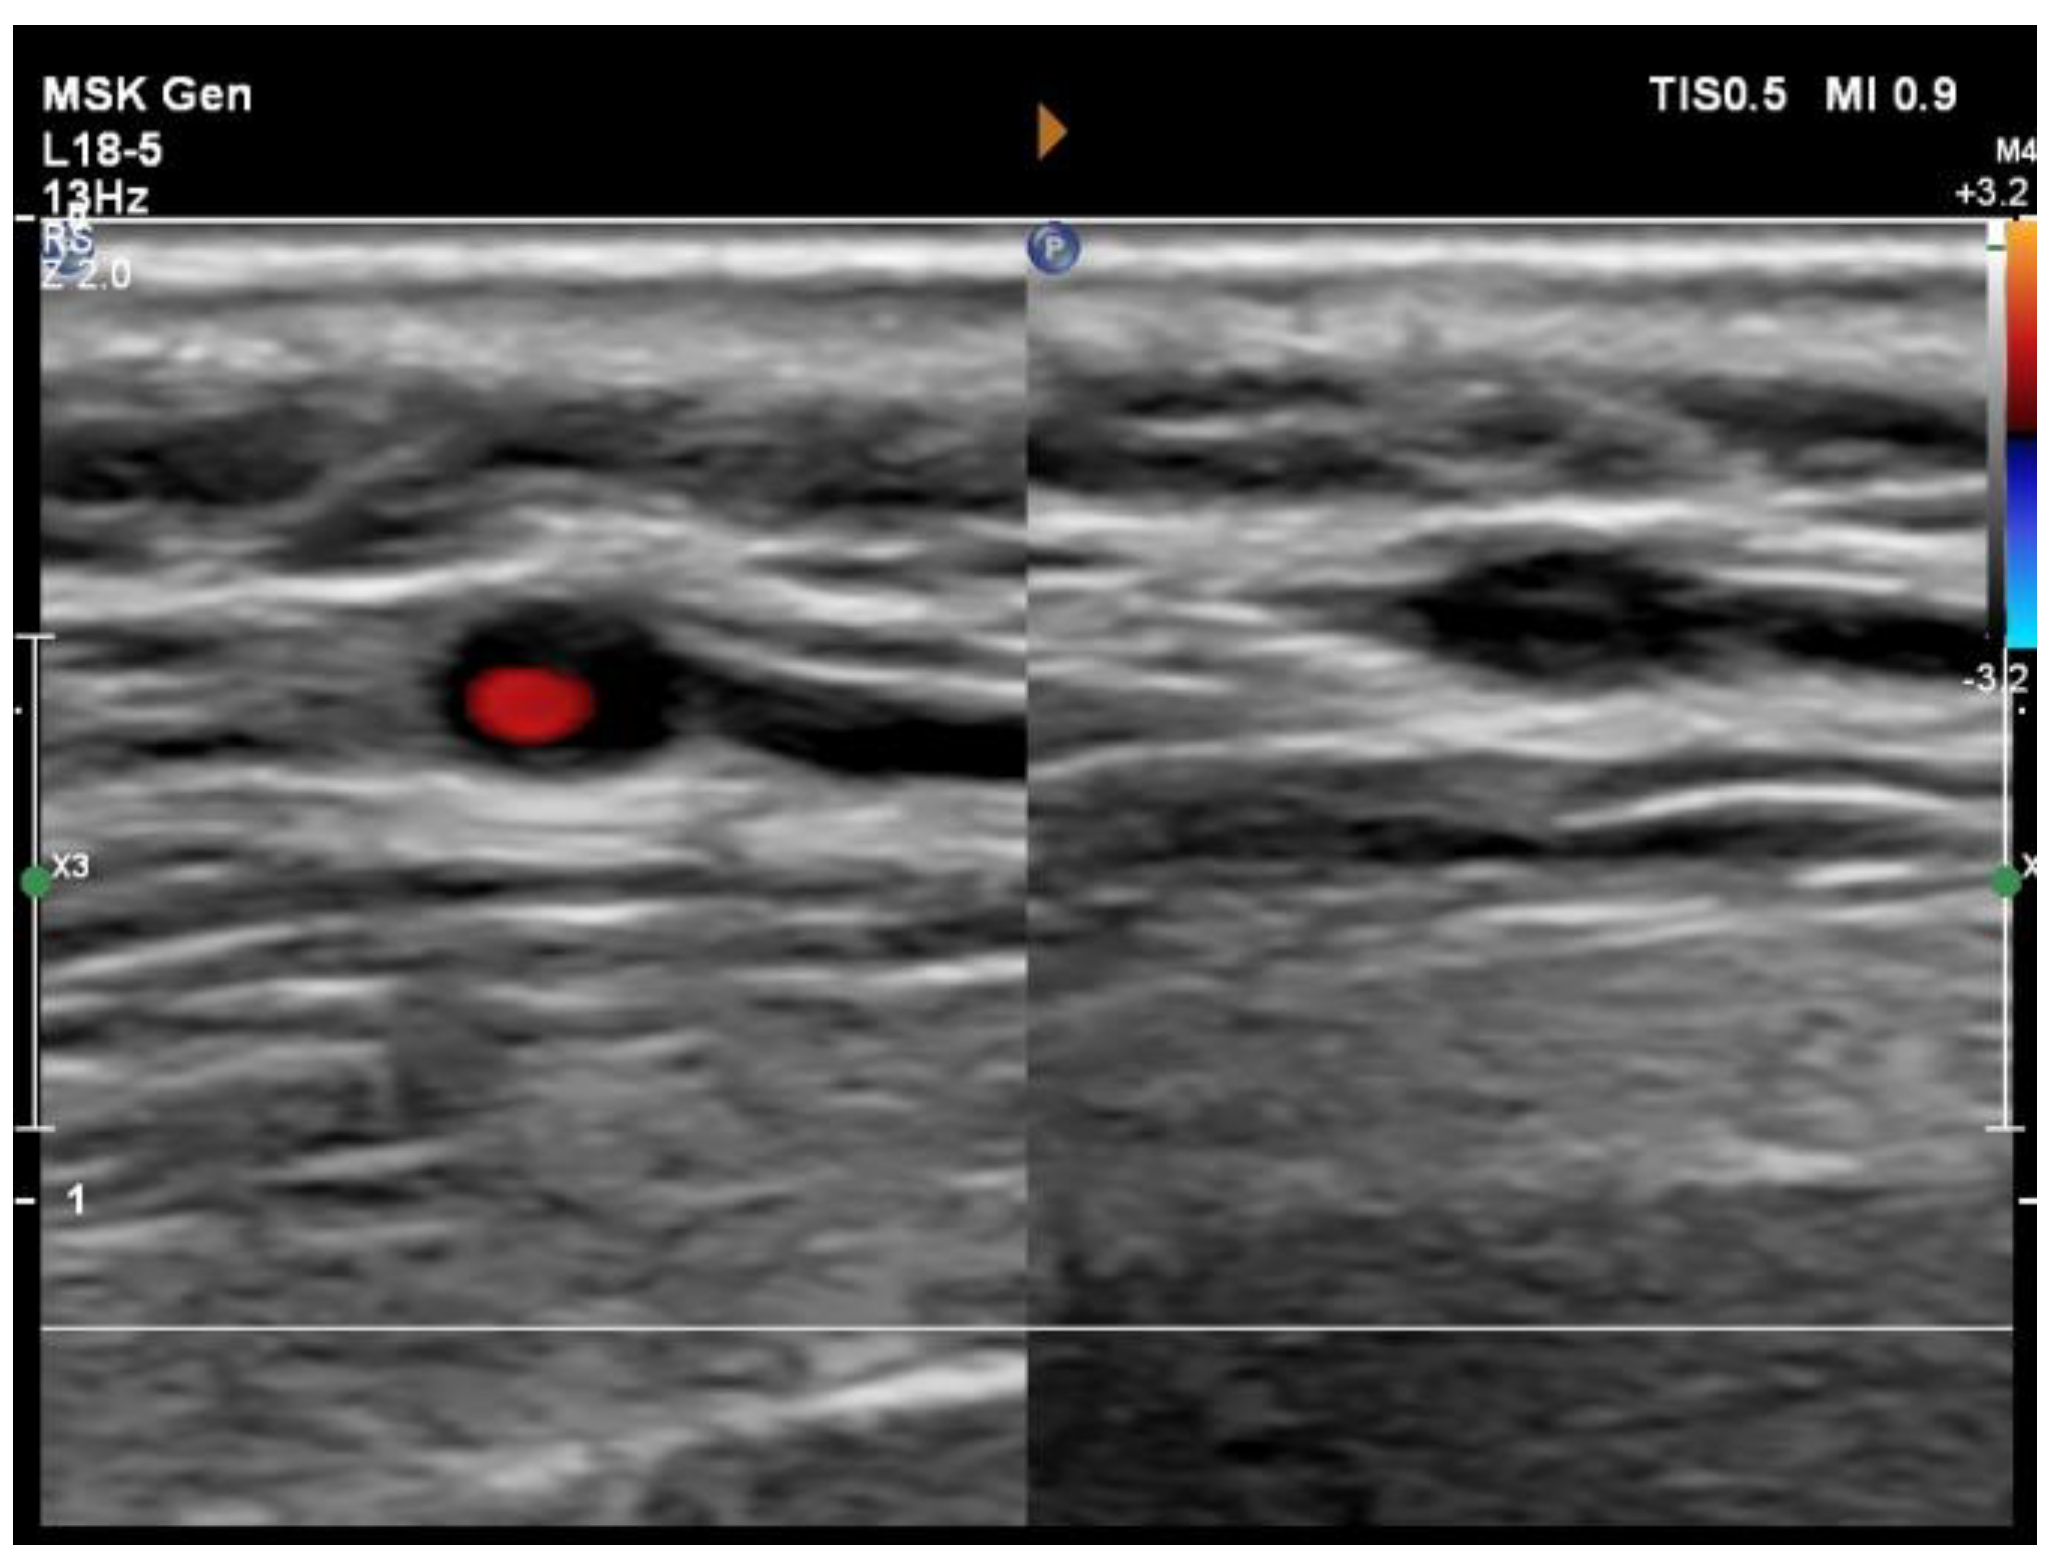

Figure 2. Detection of arterial inflammation by “compression sign”. Pressure applied with an ultrasound probe collapses the artery. The resulting restriction of blood flow is confirmed by the absence or limitation of a Doppler signal in the arterial lumen. However, the thickened inflamed arterial wall remains visible as a hypoechoic area contrasting with the mid-echogenic to hyperechoic surrounding tissue [5].